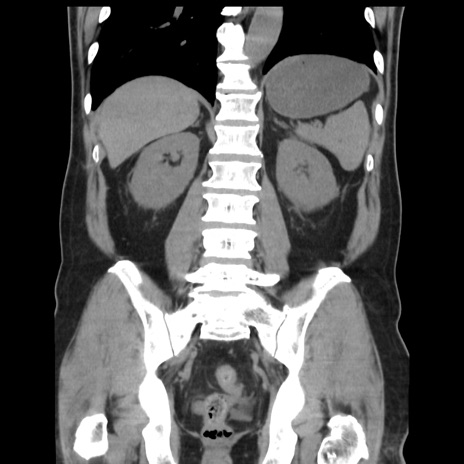

症例16(冠状断像)

【症例】 70歳代男性

【主訴】 腹痛、嘔吐

【現病歴】 約1ヶ月前より間欠的に腹痛と嘔吐あり、当院消化器内科を受診したところCTで多発する肝臓のLDAを指摘され、精査中であった。以降は消化器症状は安定していたが、2日前より嘔気と腹痛があり、同日より排便・排ガスが消失した。改善認めず、 本日、救急外来を受診した。

【既往歴】 大腸ポリープ切除後。

【身体所見】意識清明・会話良好、BT 36.3℃、BP 127/80mmHg、 P 80bpm、腹部:膨満あり、平坦・軟、上腹部正中および下腹部正中に圧痛あり、反跳痛なし、筋性防御なし。

【データ】WBC 7200、CRP 0.77